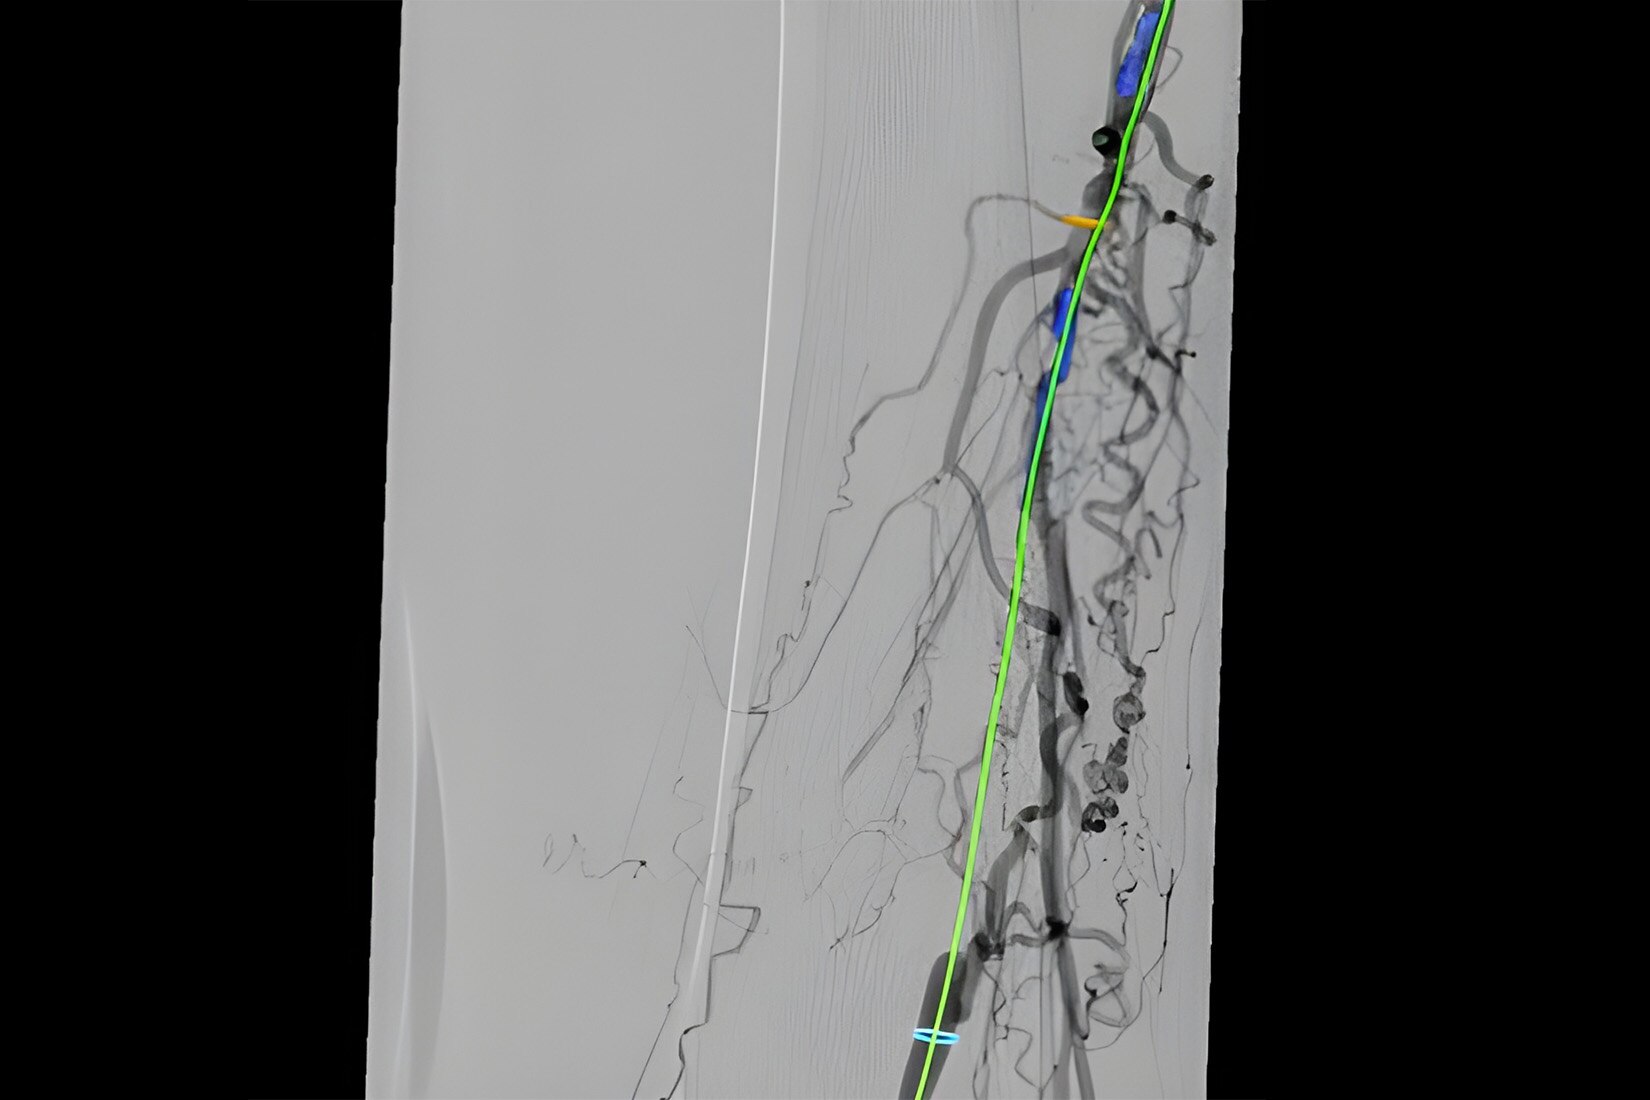

Guide

Select from the sub-volumes of vessels, centerlines, calcifications and landmarks to overlay on live fluoroscopy for 3D fusion guidance, with digital zoom, to guide recanalization.

Import segmented anatomy, centerline and landmarks and overlay them on live fluoroscopy on the frontal or lateral plane for 3D fusion guidance.